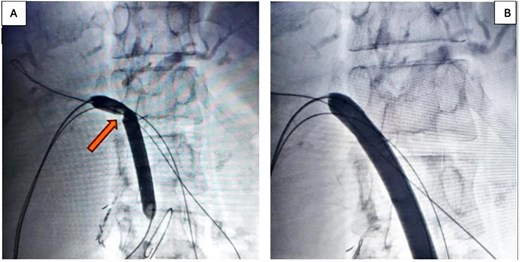

In the stage 2 procedure (15 days later), Spyglass Discover cholangioscopy was performed using the matured tract. Cholangiography was performed through the catheter, identifying the persistence of intrahepatic stones. The catheter was removed, and using the Seldinger technique, the fistulous tract was progressively dilated to 13 Fr to place an 11/13 Fr Navigator introducer. Through this, the single-operator Spyglass Discover - Boston Scientific choledochoscope was advanced, navigating toward the right and left main hepatic branches. Electrohydraulic lithotripsy (EHL) was applied to the stones, completely fragmenting them. Subsequently, endoluminal plasty of the anastomosis was performed with a 10 × 60 mm balloon (Fig. 2A and 2B), and a 10 × 57 mm biodegradable stent was implanted. Irrigation is then performed with 300 milliliters of saline solution to sweep the stone fragments toward the jejunal loop. The final cholangiography demonstrated adequate contrast flow throughout the right and left biliary trees and toward the loop (Fig. 3A). An 8 Fr feeding tube was left in segment VI to secure the path in case of complications with the stent and was left connected to a free-fall collection bag. Total procedure time was 180 minutes.

(A) 10 × 60 mm percutaneous balloon fully inflated at the anastomosis level (arrow shows the notch formed at the stenosis level); (B) Projection after performing endoluminal plasty for 3 minutes, maintaining the same inflation pressure.